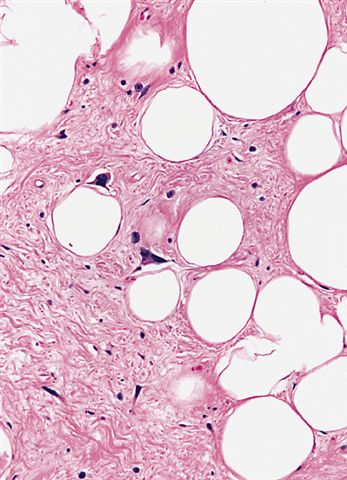

Microscopic (histologic) images

Contributed by Michael Clay, M.D., Melanie Bourgeau, M.D. and AFIP

Morphologic variability:

- Lipoma-like subtype

- Most common subtype

- Scattered atypical cells may be diffuse or exceedingly rare

- Frequently contains lipoblasts

- Grossly, can be indistinguishable from lipoma

- Depends on subtype, generally composed of mature fat with variably sized adipocytes and bands of fibrotic stroma containing spindle cells with enlarged, hyperchromatic nuclei

- Can be markedly atypical

- Cellularity is low and mitotic figures are uncommon

- Atypical cells are more commonly found in fibrous septa and in a perivascular distribution